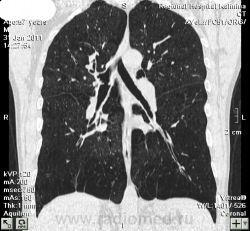

Панлобулярная эмфизема

Панлобулярная эмфизема, в отличие от центрилобулярной, все-таки не часто встречается.

Насколько я знаю, центрилобулярная эмфизема характеризуется тем, что деструкция альвеолярных стенок начинается от центра легочной дольки, поэтому на КТ мы, как правило, видим множественные мелкие полости, не граничащие друг с другом. При панлобулярной же эмфиземе легочная долька поражается равномерно, поэтому понижение плотности легкого происходит сразу на крупном участке, равномерно, без видимых границ между полостями. Этот последний вид эмфиземы происходит из-за недостаточности какого-то фермента и считается генетически обусловленным.

Буллезная же эмфизема с нозологической точки зрения - это не отдельный вид. Буллой принято называть эмфизематозную полость >2 см в диаметре.

альфа 1 ингибитор протеаз